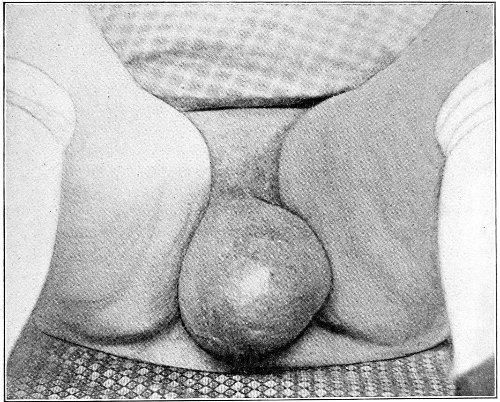

Suppuration of the vulvo-vaginal gland is accompanied by marked swelling and peripheral edema. The swelling may extend to the anus, and is of characteristic shape (Fig. 17). The pain is always severe. Fluctuation is first apparent on the inner surface of the labium majus. If the condition is not treated, one or more fistulous openings appear below the orifice of the duct, and the pus is discharged. The condition then becomes chronic. The fistulous openings persist. Acute inflammation disappears from the gland, leaving it in a condition of hypertrophic induration. A thin, milky or greenish, purulent fluid may be pressed out of the duct or the fistulous openings. Infection from this discharge may be communicated to man, or may ascend the genital 40 tract, producing inflammation of the endometrium or of the Fallopian tubes.

Fig. 17.—Abscess of right vulvo-vaginal gland.